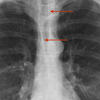

Anterior junction line